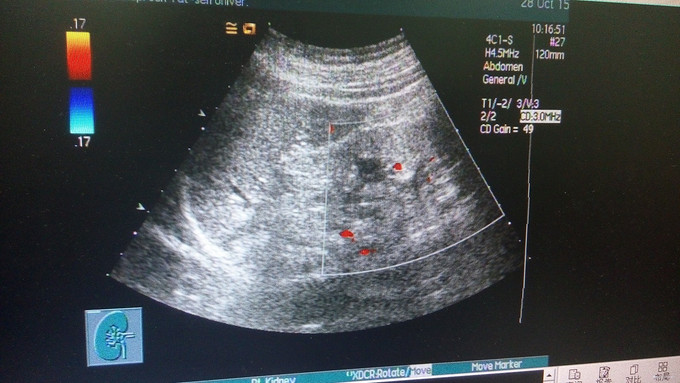

查体:血压135/84mmHg,双下肢可凹性浮肿,眼结膜苍白。 辅查:肌酐924.00umol/L,铁5.7umol/L,总铁结合力30.5umol/L,血红蛋白73g/L,尿素32.13mmol/L,尿酸499umol/L。 肾脏B超显示慢性肾功能不全声像,双肾缩小。对患者进行肾小球滤过率估计:eGFR为4mL/min/1.73mE2。